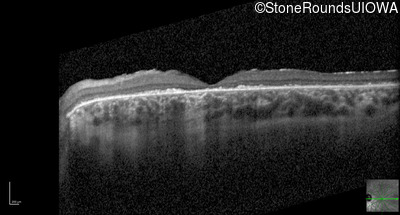

Optical Coherence Tomography - Left - 20/100 -2 sc

Exemplar / OCT Stack

OCT Stack